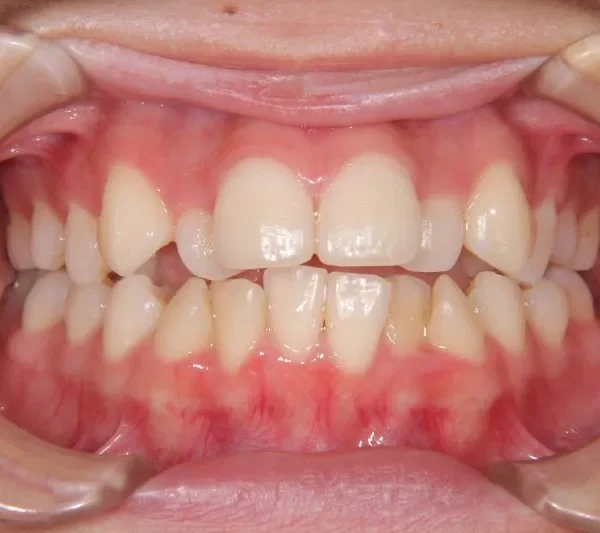

• 治療終了後

治療終了後

叢生は解消し、口元が大幅に引っ込み、下顎面高も縮小しました。

主訴が改善され、ご満足頂きました。